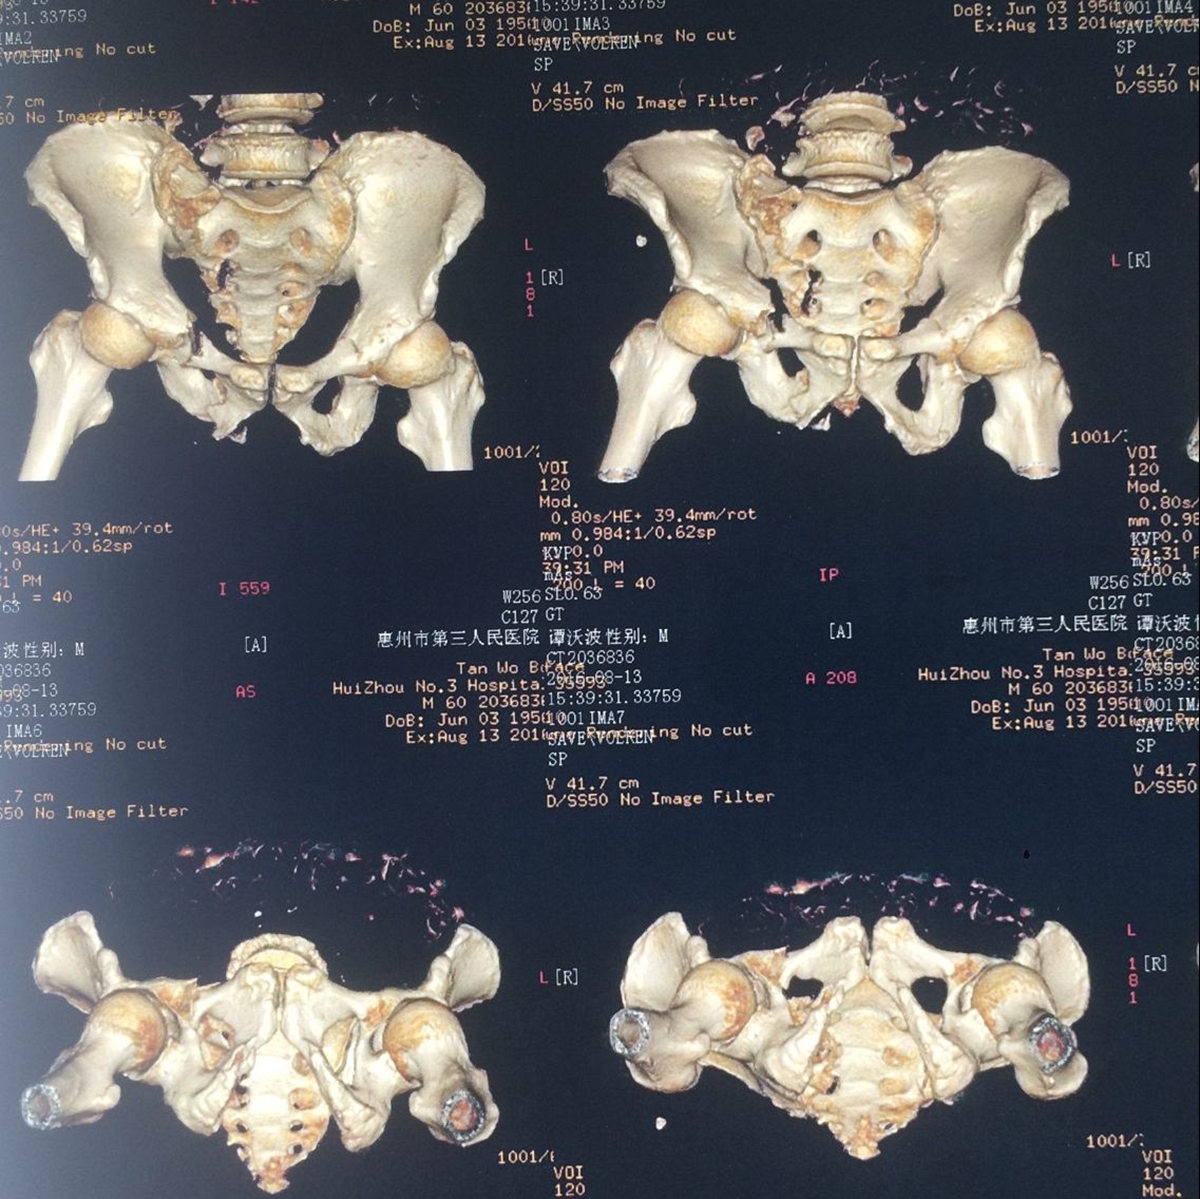

該患者為雙前臂橈尺骨遠(yuǎn)端多發(fā)粉碎骨折,骨盆多發(fā)骨折(雙側(cè)恥骨上下支骨折、右髖臼骨折、右骶骨粉碎性骨折),腰椎多發(fā)骨折。骨盆骨折的手術(shù)治療在創(chuàng)傷骨科而言,難度大、技術(shù)要求高,較容易出現(xiàn)相關(guān)并發(fā)癥。

患者骨盆骨折術(shù)前X片及CT片情況